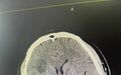

不出医生所料,头颅磁共振提示,吴先生确实为脑梗。 医生赶紧为其办理住院手续。

该院神经内科姚银旦副主任医师马上决定为其进行脑动脉造影检查。脑动脉造影发现,吴先生颅内血管存在多发中—重度狭窄。可以说,30岁的年龄,血管比60岁老人的血管还要苍老。